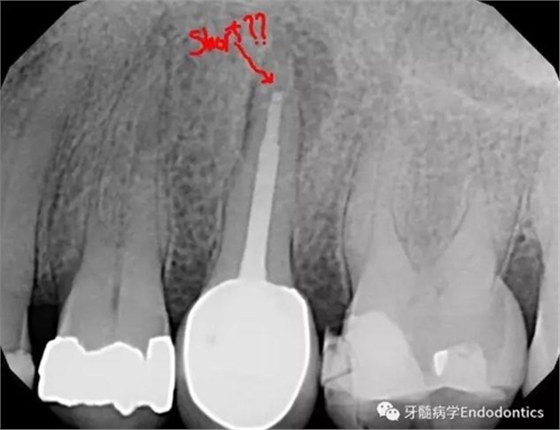

圖3.術(shù)后X線片示根充物距離根尖有3mm的距離